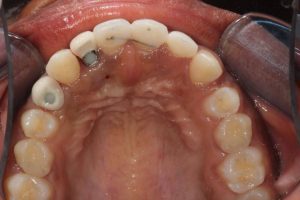

Upper Anterior Implants with Orthodontic Treatment

This patient was born with missing teeth and as a result the teeth that were present moved into these spaces. We started with orthodontic treatment (braces – undertaken by Dr Zaid Esmail) to move the teeth into the correct position and create the space needed for the dental implants. The implants were then placed towards the end of the braces treatment and the crowns fitted once the teeth were fully aligned.